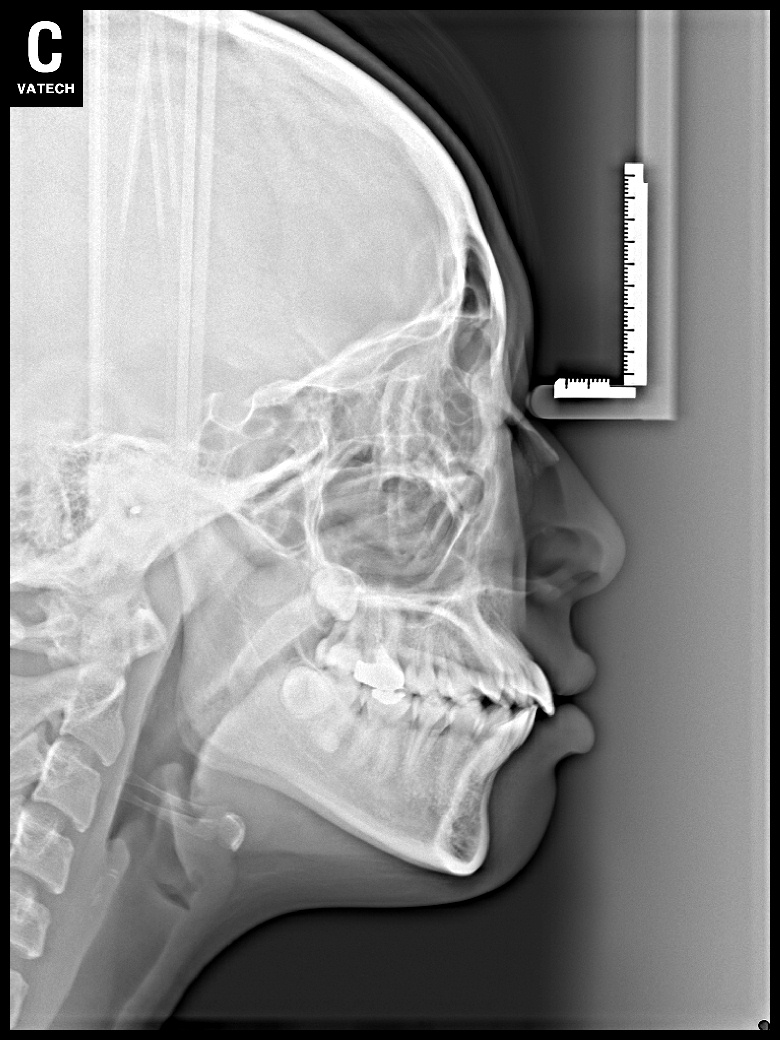

치료 후 사진입니다.